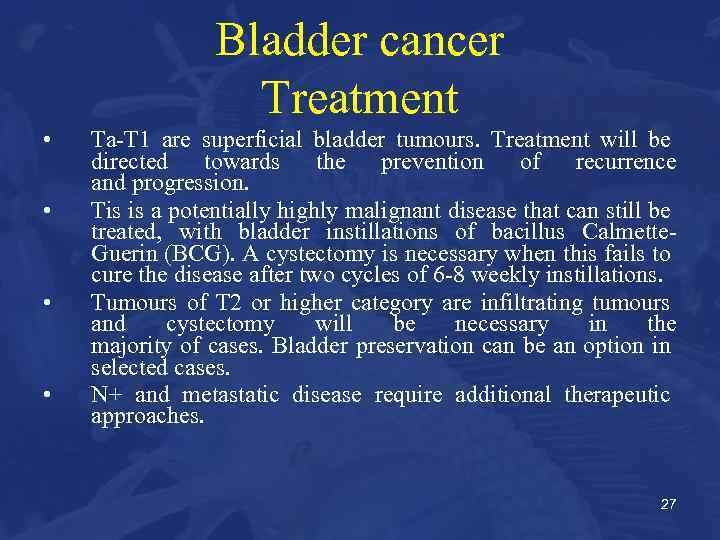

Bladder cancer Treatment • • Ta-T 1 are superficial bladder tumours. Treatment will be directed towards the prevention of recurrence and progression. Tis is a potentially highly malignant disease that can still be treated, with bladder instillations of bacillus Calmette. Guerin (BCG). A cystectomy is necessary when this fails to cure the disease after two cycles of 6 -8 weekly instillations. Tumours of T 2 or higher category are infiltrating tumours and cystectomy will be necessary in the majority of cases. Bladder preservation can be an option in selected cases. N+ and metastatic disease require additional therapeutic approaches. 27